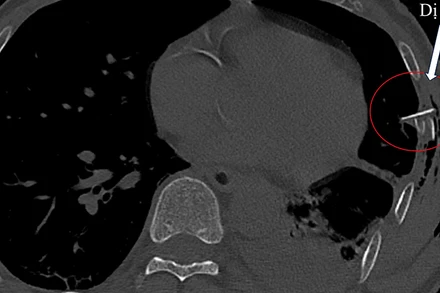

Sáng 1/4, Bệnh viện đa khoa Trung ương Quảng Nam cho biết, đơn vị vừa cứu sống một bệnh nhân nam (63 tuổi) bị tai nạn giao thông gây chấn thương thủng phổi do mảnh gãy của xương sườn đâm vào.

Chiều 28/12, Bác sĩ chuyên khoa 2, Nguyễn Tam Thăng, Phó Giám đốc Bệnh viện đa khoa Quảng Nam cho biết, bệnh viện vừa cứu sống một bệnh nhân mất máu nguy kịch do vết thương thấu ngực. Đây là bệnh nhân đầu tiên bị mất máu nguy kịch được cứu sống, sau 10 ngày tiếp nhận, phẫu thuật và điều trị.